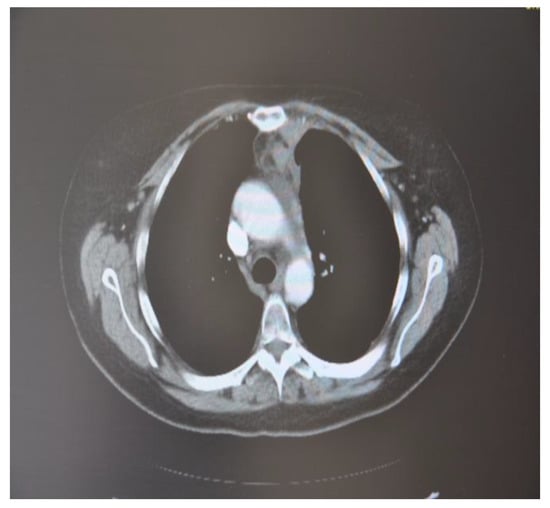

In October 2018, a 24-year-old patient arrived at our cryosurgery unit with the results of a CT scan. The presence of bilateral pulmonary and mediastinal lymph node metastases close to the esophagus was highlighted (Figure 6).

Figure 6. CT scan images indicate the presence of bilateral pulmonary and mediastinal lymph node metastases close to the esophagus. The arrow indicates the tumor’s location.